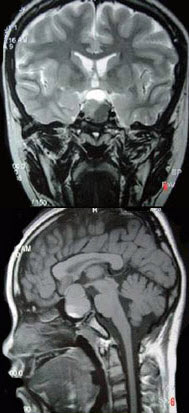

男,47岁,视物模糊数月,头痛、恶心、呕吐3天,行MRI检查如图,最可能的诊断为( )

A:颅咽管瘤

B:脑膜瘤

C:垂体瘤并出血

D:蛛网膜囊肿

E:表皮样囊肿